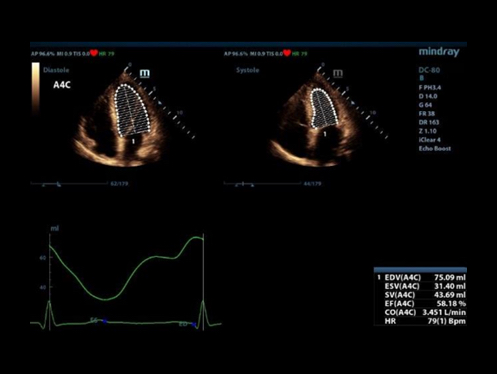

eXceptional intelligence

Kecerdasan di seluruh alur kerja yang ada

Untuk meningkatkan efisiensi pemindaian dengan akurasi dan konsistensi yang lebih tinggi, X-Insight memberikan kecerdasan luar biasa di seluruh alur kerja ujian, mulai dari akuisisi pesawat hingga pengoptimalan gambar, dan dari penghitungan hingga protokol ujian.